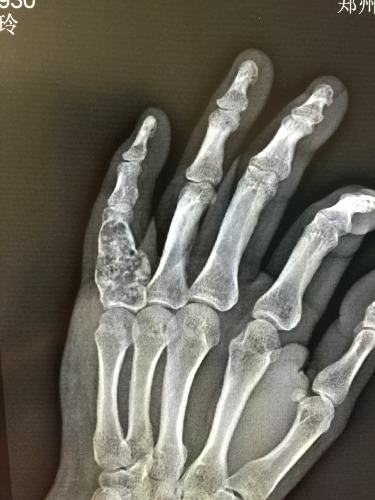

骨肿瘤x线图片

骨肿瘤x线图片,骨肉瘤x线图片

疾病百科 疾病介绍 常见的x线表现为侵袭性溶骨病损,同时有肿瘤

看图学习:骨肿瘤的x线诊断

骨肉瘤x线图片

骨肿瘤x光片图

手指骨肿瘤图片